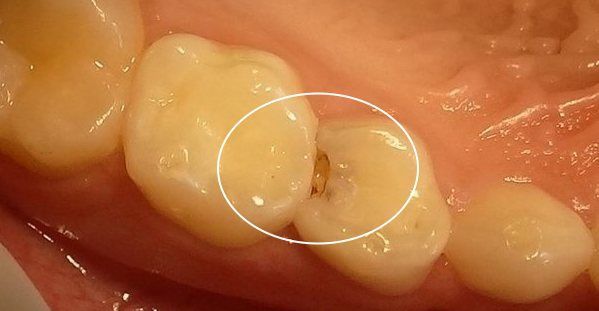

两颗牙齿接触的地方,看似密不可分,但它们之间其实是存在着间隙的。这些间隙很窄,你可能用肉眼看不出来。

如果这些区域长期没有得到有效的清洁,细菌就会在里面扎堆生长,这最后的结果,很可能就会演变成蛀牙。